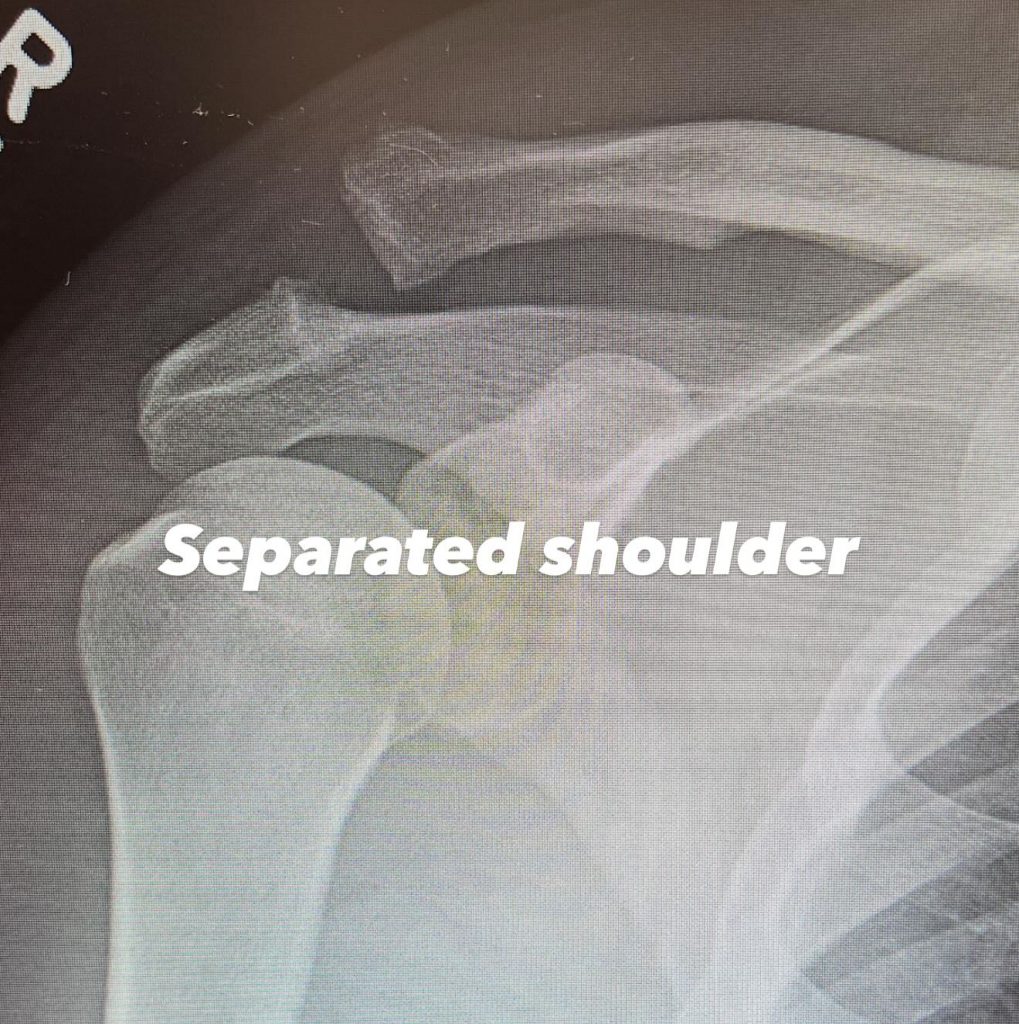

Попал под наблюдение врачей актер из-за отрыва акромиона. Это травма, возникающая при разрыве или растяжении связок в месте соединения ключицы с лопаткой. На одном из рентгеновских снимков видно повреждение, а именно разрыв плечевого сустава, а на другом виднеется уже вмонтированный винт для стабилизации сустава.